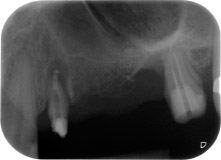

One month later, on the day of surgery, pain and inflammation at tooth 24 were minimal, but mobility of Miller class 2 was still present. After opening the flaps and cleaning the periapical and peri radicular infected tissue, the extent of the bone defect became obvious (Figs. 2 and 3).

At the buccal root, all vestibular and distal bone was missing. Attachment was essentially restricted to the palatal root, underlining the preliminary poor prognosis. Tooth 27 also showed a reduced horizontal attachment and a minimal apical rarefaction (cf. Fig. 1) without clinical symptoms.